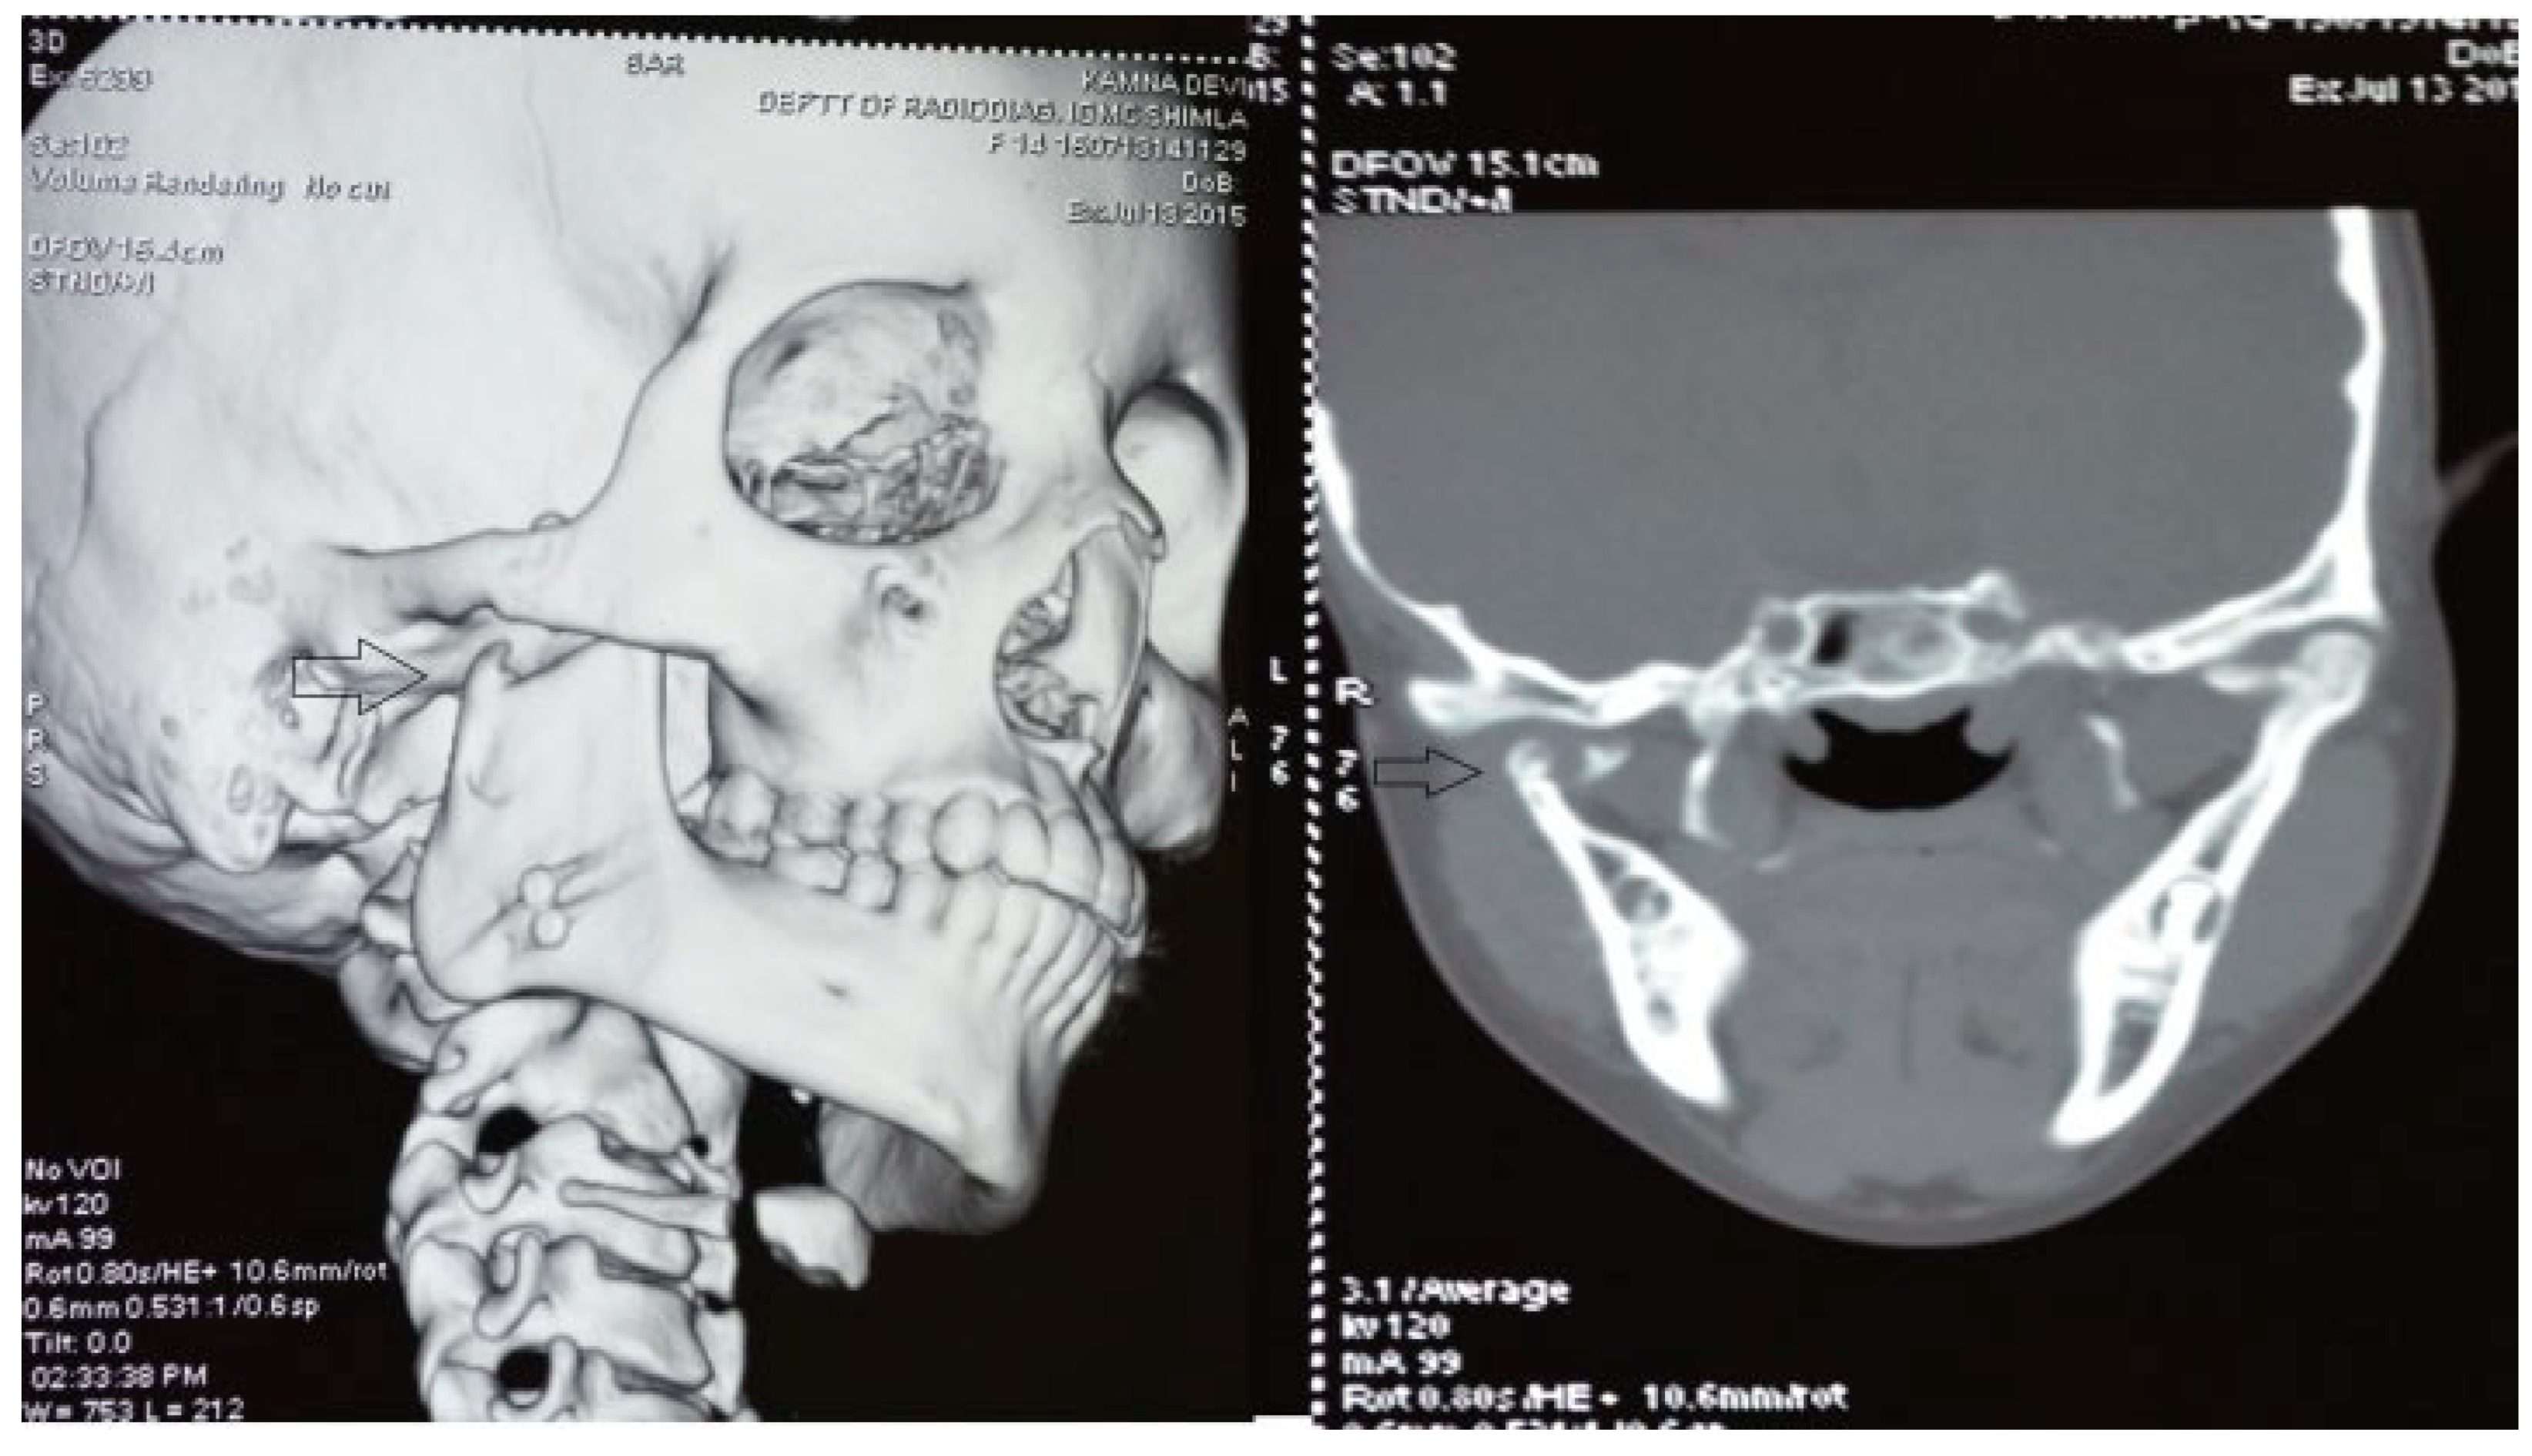

Figure 4. Postoperative coronal CT and three-dimensional CT scan with temporomandibular joint (TMJ) ankylosis at 6 years of follow-up depicting neocondyle (black arrow) formation (CCG graft with temporalis muscle interpositioning was done with respect to right TMJ).

The unique ability of the CCG to remodel into neocondyle could be well appreciated on the digital OPG and CT scan of the patient. The length and width of the neocondyle was very much comparable to the length of the condyle on the unaffected side at 6 years follow-up. Thus, the neocondyle formed using the costochondral cartilage was identical to the unaffected mandibular condyle both structurally and functionally. Poor socioeconomic conditions and lack of awareness coupled with poor primary health care facilities lead many of these unfortunate patients to live with this debilitating condition well into adulthood. Five such adult patients with age ranging from 17 to 36 years reported to us for treatment of TMJ ankylosis. In all these patients, ankylotic bony mass extends beyond the boundaries of the joint capsule. Alloplastic reconstruction after the release of ankylosis was our method of treatment, although high cost of condylar prosthesis led us to use 2.4 mm condylar head reconstruction plate along with temporalis muscle interpositioning in these patients. Interpositional grafts may fail to restore the ramal height in bilaterally ankylosed adult patients, so alloplastic condylar reconstruction may become the preferred choice. Advantages of alloplastic TMJ reconstruction are that the physical therapy can begin immediately, there is no need for a secondary donor site, surgery time is decreased, and alloplasts can be constructed in such a way as to mimic the normal anatomic contours of the structures they are to replace [17,18]. Wolford and Karras have suggested autologous fat transplantation as a useful adjunct to prosthetic TMJ reconstruction, as it minimizes the occurrence of excessive joint fibrosis, heterotopic calcification, and improves the range of motion [19]. However, they have categorically stated in their discussion that heterotopic bone formation is seen in multiple operated joints and joints with previously failed alloplastic implants. Another method to combat heterotopic bone formation is the use of 10 Gy of irradiation in five fractionated daily doses in the immediate postoperative period [20]. In our series, none of the patients reported with heterotopic bone formation possibly because they had undergone a single surgical procedure for managing TMJ ankylosis. The risk of fossa perforation could have been taken care by interpositioning of temporalis muscle in all these patients.

Temporalis muscle was used in seven patients and temporalis fascia was used in two patients. In our series, using temporalis fascia as an interpositional material in the postoperative MIMO was 37 mm. Temporalis fascia has the disadvantage of being thinner, taut, and nonelastic. Long-term follow-up showed premature contact of teeth on the operated side in both the patients and the ramal height was not maintained. When the temporalis muscle was used as interpositional material, we based our flap on one of the branches of deep temporal arteries to maintain its vascularity and the flap was turned over the zygomatic arch and placed into the glenoid fossa. Temporalis muscle provided us with more bulk to obliterate the joint space and was sandwiched between the chondral end of the CCG and temporal bone. After appropriate positioning has been established, the muscle is sutured in both the anterior and posterior directions. Moreover, there is no hematoma formation and hence had better long-term stability. In patients where temporalis muscle was used, the MIMO was 41 mm and ramal height was maintained in all the cases (Figure 7 and Figure 8). The ramal height was preserved in most of our cases possibly due to unilateral ankylosis with compensation by the contralateral mandibular unit. Management of ankylosis in children can be very challenging and our aim was to correct retrognathia in bilateral cases and reduce the possibility of further asymmetry in unilateral cases. Growth center transplantation using CCGs was done in seven growing children in the 6- to 13-year age group. The uses of this biologically compatible autograft in reconstruction are benefits of growth potential and ability to remodel into a neocondyle with time. Unpredictable growth pattern of the CCG, midline shift, and donor site morbidity are some of the disadvantages of this technique. Overgrowth of the graft has been attributed to the use of a large cartilaginous cap; hence, only 1 to 2 mm cartilaginous cap must be used to avoid such complications [13,14,15]. We assessed the same using panoramic radiographs during follow-ups. The CCGs showed excellent mandibular growth along with complete integration of graft into the recipient site over the passage of time in all seven cases. The CCG was harvested from the sixth rib (contralateral side) using submammary incision and was secured using three 2-mm titanium screws at the recipient site. Due to the close proximity of the chondral cartilage to the base of skull, we routinely interposed temporalis muscle in these patients. The muscle pedicle acted as an artificial disc as well as a barrier between the base of skull and chondral cartilage (Figure 9). Early and vigorous mobilization is important to prevent postoperative adhesions and reankylosis [16]. The postoperative MIMO in seven patients was 41.5 mm. Asymmetry in the form of deviation of chin was found in one patient during long-term follow-up, where CCG overgrowth led to the deviation of the chin to the contralateral side.